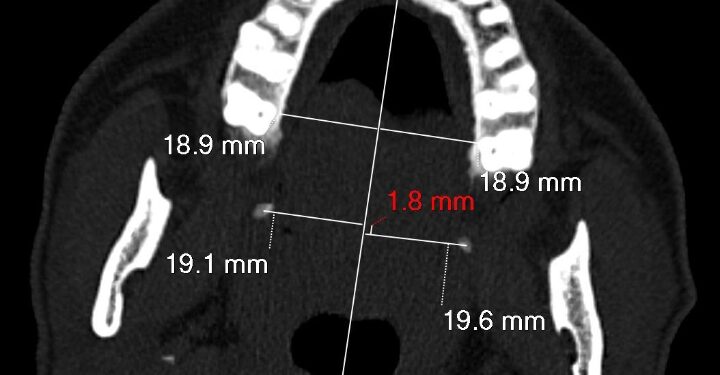

كما كشفت الدراسة عن إمكانية استخدام خط وهمي يتم رسمه على التصوير الطبقي المحوري، أُطلق عليه اسم “Bin Turayki’s Line” نسبة إلى مكتشفه الدكتور هيثم بن عبدالله بن تريكي، ليساهم في تسهيل تشخيص هذه الحالات مستقبلًا.